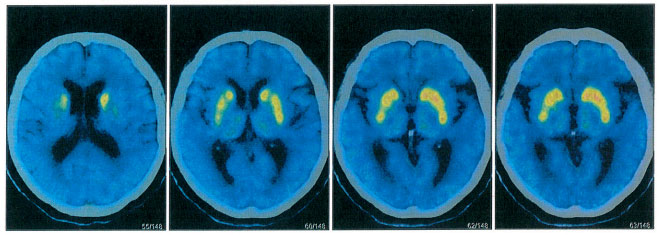

为了进一步鉴别诊断,张静波主任团队为患者进行了PET磁共振检查(多巴胺转运体、葡萄糖代谢、Aβ蛋白分子影像学鉴别),进一步鉴别帕金森病和老年痴呆。张静波主任介绍,除了在恶性肿瘤的诊断、治疗前评估与疗效评估等应用,PET在神经系统疾病的诊断上也应用广泛。在脑显像中,PET能提供病理生理学和分子水平信息,为神经系统疾病(尤其是神经退行性疾病和脑肿瘤等)的诊疗决策提供有力的证据。

▲ 检查结果:多巴胺转运体异常

PET影像结果示:脑部18F-AV45结果:双侧大脑半球皮质Aβ(β-淀粉样蛋白)未见异常沉积。脑部18F-FDG结果:双侧额叶、双侧尾状核、中脑FDG代谢减低;双侧小脑FDG代谢减低。脑部11C- CFT结果:双侧尾状核、双侧壳核前部、双侧壳核后部DAT(多巴胺转运体)分布减低,右侧明显。

张静波主任指出,如果是帕金森病,多巴胺转运体是以进行性壳核损害为主,所以排除帕金森病。但是双侧大脑半球皮质Aβ未见异常沉积,因此也排除老年痴呆。诊断方向进一步明确,张静波主任进一步考虑为帕金森叠加综合征。帕金森叠加综合征是有帕金森病的综合征的一些临床表现,但是伴有其他的一些神经系统变性疾病的综合征,比如说患者有可能有进行性核上性麻痹、皮质基底节变性、多系统萎缩和额颞叶痴呆等疾病。最终,经会诊,确诊额颞叶痴呆合并帕金森综合征。